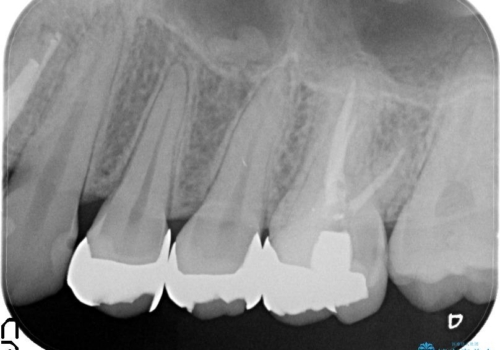

- 笑って見えるところの金属を白くしたいとのことで来院されました。

相談の結果、左上4,5のメタルインレーをセラミックインレーへと変更することとしました。

左上6は希望されなかったため、左上4,5のみをセラミックにやりかえています。